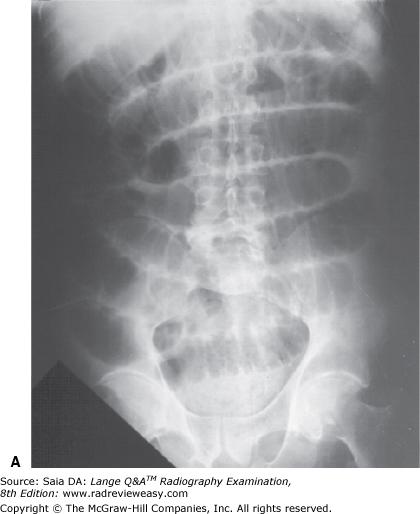

In which of the following positions was the radiograph in Figure A taken?

A RPO

B LPO

C AP axial

D Right lateral decubitus

-The pictured radiograph is an oblique position of the large bowel, illustrating an "open" view of the hepatic/right colic flexure and ascending colon, with the splenic/left colic flexure superimposed on the descending colon. Therefore, the radiograph must have been made in either an RAO (if the patient was prone) or an LPO (if the patient was supine) position. The LAO and RPO positions are used to demonstrate the splenic/left colic flexure and descending colon free of self-superimposition. AP or PA axial is generally used to visualize the rectosigmoid colon.